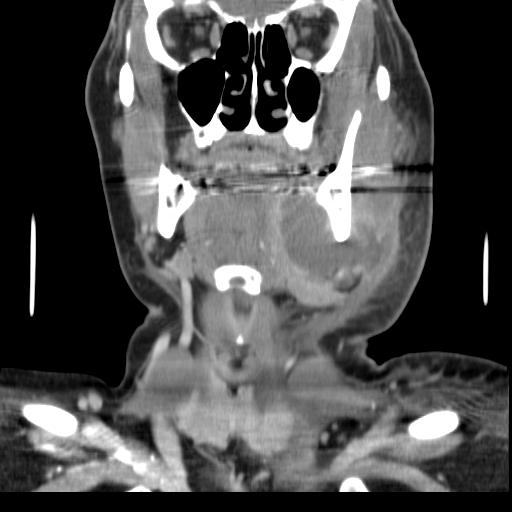

치아 농양을 치료하지 않고 방치하면 뼈를 관통하고 연조직으로 확장될 정도로 커져 골수염 및 봉와직염으로 진행될 수 있다. 거기에서 감염은 최소 저항 경로를 따라 내부 또는 외부로 퍼질 수 있다. 감염 경로는 감염된 치아의 위치, 뼈, 근육 및 근막 부착 부위의 두께와 같은 요인의 영향을 받는다.

내부 배농은 성장하는 감염이 감염 주변 조직 내에서 공간을 만들기 때문에 더 우려된다. 즉시 입원이 필요한 심각한 합병증으로는 성장하는 감염과 봉와직염의 조합인 루트비히 협심증이 있으며, 이는 극단적인 경우 기도를 닫아 질식을 유발할 수 있다. 또한 감염은 조직 공간을 따라 종격동으로 퍼져 심장과 같은 생명 유지 기관에 심각한 영향을 미칠 수 있다. 또 다른 합병증은 일반적으로 위쪽 치아에서 발생하며, 패혈증이 경로를 통해 이동하여 심내막염, 뇌 농양 (극히 드물게), 또는 수막염 (또한 드물게)으로 이어질 수 있는 위험이 있다.